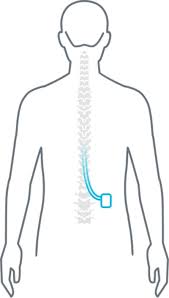

OPIS PROCEDURY TLIF – KROK PO KROKU

Pozycjonowanie

- Pozycja na brzuchu,

- Ochrona punktów ucisku,

- Neuromonitoring (SSEP/EMG – zalecany).